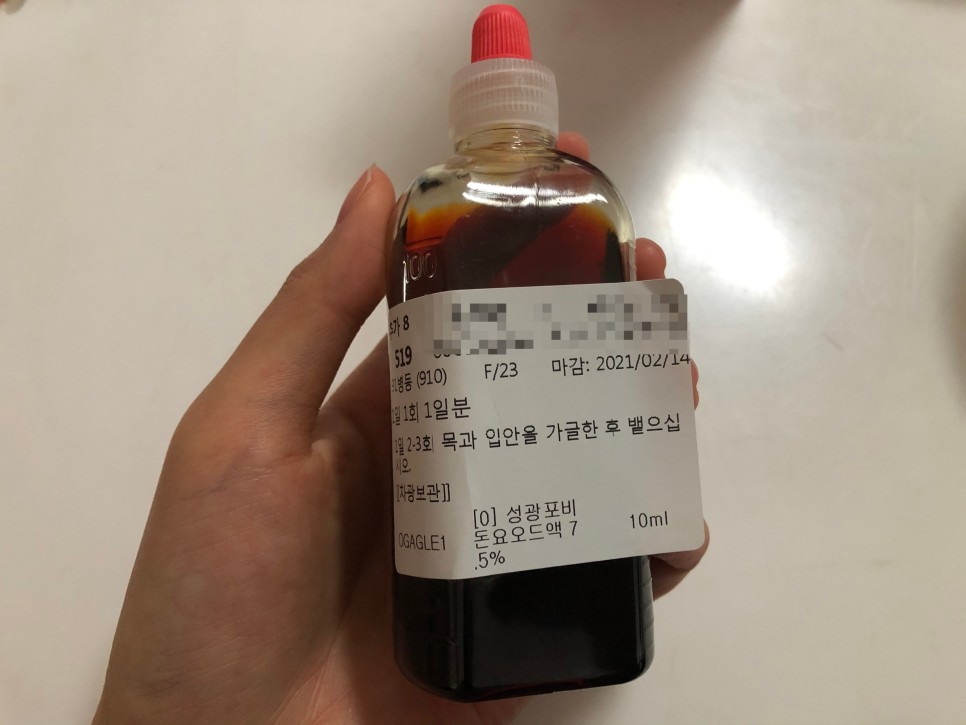

이건 수술하면 주는 우의약이지만 하루에 2~3회씩 양치질을 하고 토하면 돼요

얼음물의 가글은 통증 완화, 지혈 등의 목적이라면 소독이라고 말씀하셨습니다!